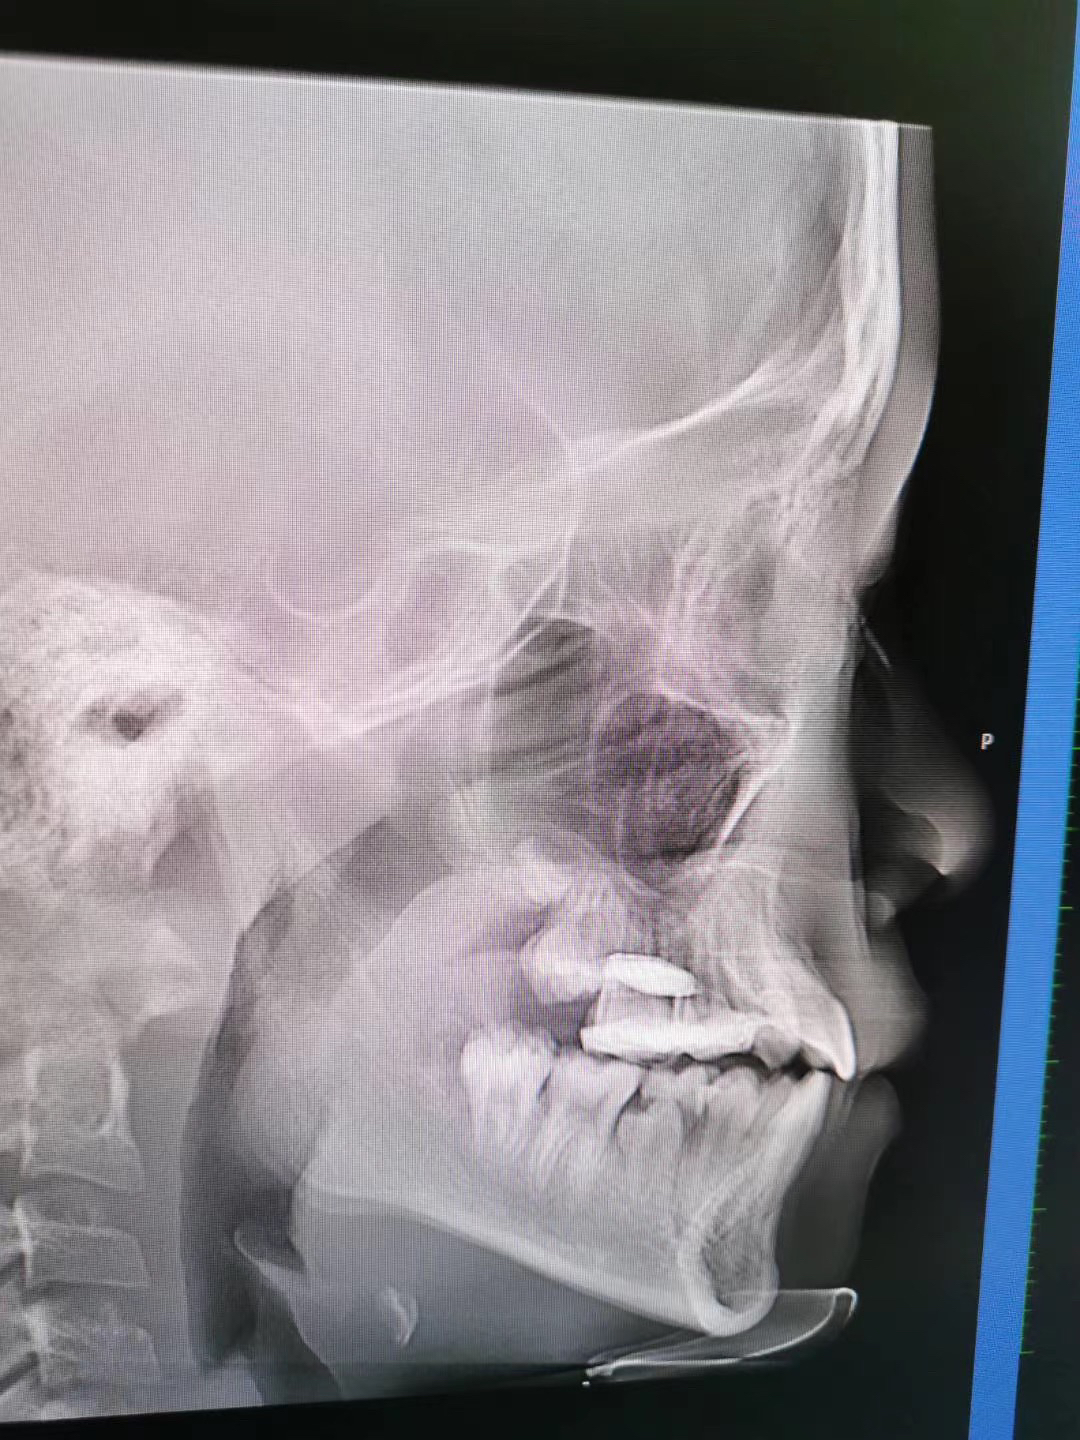

因为一下牙齿情况要早些干预,毕竟地包天这个牙齿情况,早发现,早干预,地包天矫正越早越好,当家长发现小孩子有地包天的趋势,就要及时咨询口腔医生,早期的时候可以通过活动矫正器简单的方法来预防和纠正不让他进一步的发展。有些小孩子乳牙期间就有地包天,家长不要以为没什么影响,一直拖延的话,会增加矫正的难度,其实有些牙齿情况会遗传的,就比如电视剧的情况,所以家长要及时注意哦!